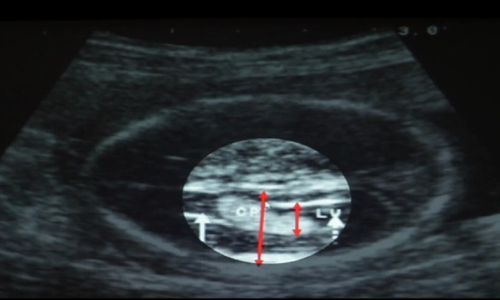

High-resolution variable frequency ultrasound imaging is increasingly being used in the noninvasive evaluation of various cutaneous diseases. It plays a complimentary role to physical examination in the assessment of cutaneous lesions.

The Color Doppler test is a popular imaging test prescribed to pregnant women during their gestation period. Not just for recording the baby's heart rate, a color doppler also checks the blood flow and fetal growth in the womb. Doppler scans are done during the third trimester, preferably during the last stage of pregnancy, to rule out any complications in the baby or the mother. In high-risk pregnancies, the test is done during the early stages.

Ultrasound is an easy and accessible screening and diagnostic tool that can be used to assess for uterine and related abnormalities. When it comes to comparing 2D vs 3D ultrasounds, how do these technologies compare? 2D ultrasound delivers a live, real-time view of the pelvis in a radiation-free process that involves high-frequency sound waves.

Fetal echocardiography is a specialized ultrasound test performed during pregnancy to evaluate the position, size, structure, function and rhythm of the unborn baby’s heart. An obstetrician is able to obtain a limited view of the baby’s heart during a routine pregnancy ultrasound.

Transvaginal ultrasound is a test used to look at a woman's uterus, ovaries, tubes, cervix, and pelvic area. Transvaginal means across or through the vagina. The ultrasound probe will be placed inside the vagina during the test.